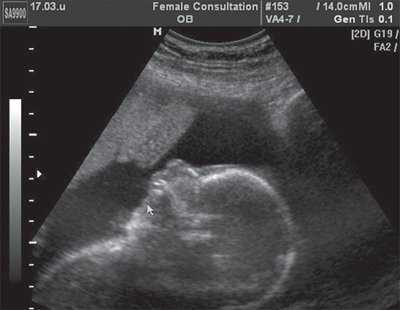

Рис. 5. Эхограмма продольного сечения грудной клетки плода. Стрелкой указан желудок плода, расположенный в его грудной клетке.

Рис. 6. Эхограмма поперечного сечения грудной клетки плода. Стрелкой указан желудок плода, расположенный в его грудной клетке.